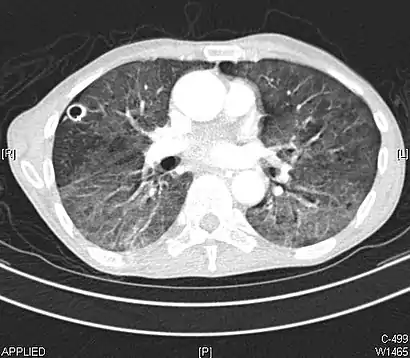

CT image in patient with COVID-19 showing bilateral ground-glass opacities at the periphery of both lungs.

Ground-glass opacity is among the most common imaging findings in patients with confirmed COVID-19.[16][17] One systematic review found that among patients with COVID-19 and abnormal lung findings on CT, greater than 80% had GGOs, with greater than 50% having mixed GGOs and consolidation.[16] GGOs with mixed consolidation has most often been found in elderly populations.[18] Several studies have described a pattern among initial, intermediate, and hospital discharge imaging findings in the disease course of COVID-19. Most commonly, initial CT imaging reveals bilateral GGOs at the periphery of the lungs. During initial stages, this is most often found in the lower lobes, although involvement of the upper lobes and right middle lobe has also been reported early in the disease course.[16][18] This is in contrast to the two similar coronaviruses, SARS and MERS, which more commonly involve only one lung on initial imaging.[19][20] As the COVID-19 infection progresses, GGOs typically become more diffuse and often progress to consolidation.[11][18] This is sometimes accompanied by the development of a crazy paving pattern and interlobular septal thickening.[18] In many cases the most severe pulmonary CT abnormalities occurred within 2 weeks after symptoms began.[17] At this point, many individuals begin showing resolution of consolidation and GGOs as symptoms improve. However, some patients have worsening symptoms and imaging findings, with further increase in septal thickening, GGOs, and consolidation. These patients may develop lung "white-out" with progression to acute respiratory distress syndrome (ARDS) requiring treatment escalation.[17][21]